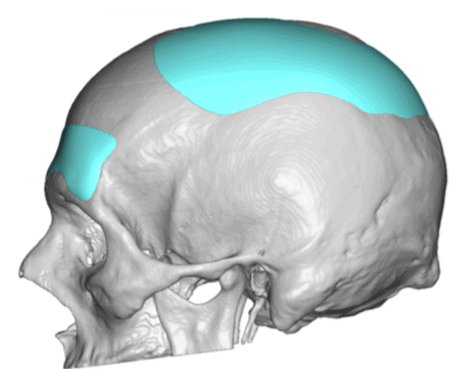

Patient 28

Desire for rounder shape to the top of the head from a congenital parasagittal deficiency skull shape.

Custom skull implant designed to fill in the parasagittal deficiencies.

Desire for rounder shape to the top of the head from a congenital parasagittal deficiency skull shape.

Custom skull implant designed to fill in the parasagittal deficiencies.